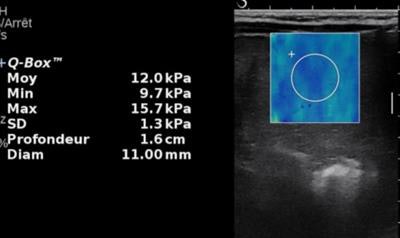

For children, multiparametric liver ultrasound to show tumoral and nontumoral liver is the first line of deeper investigation, after the initial diagnosis of a liver mass. Different techniques should be used including grayscale, Doppler, elastography for fibrosis, Micro-Doppler to discern the vascularization of the tumor, and contrast-enhanced ultrasound to assess tumor behavior, and differentiate between malignant and benign lesions.